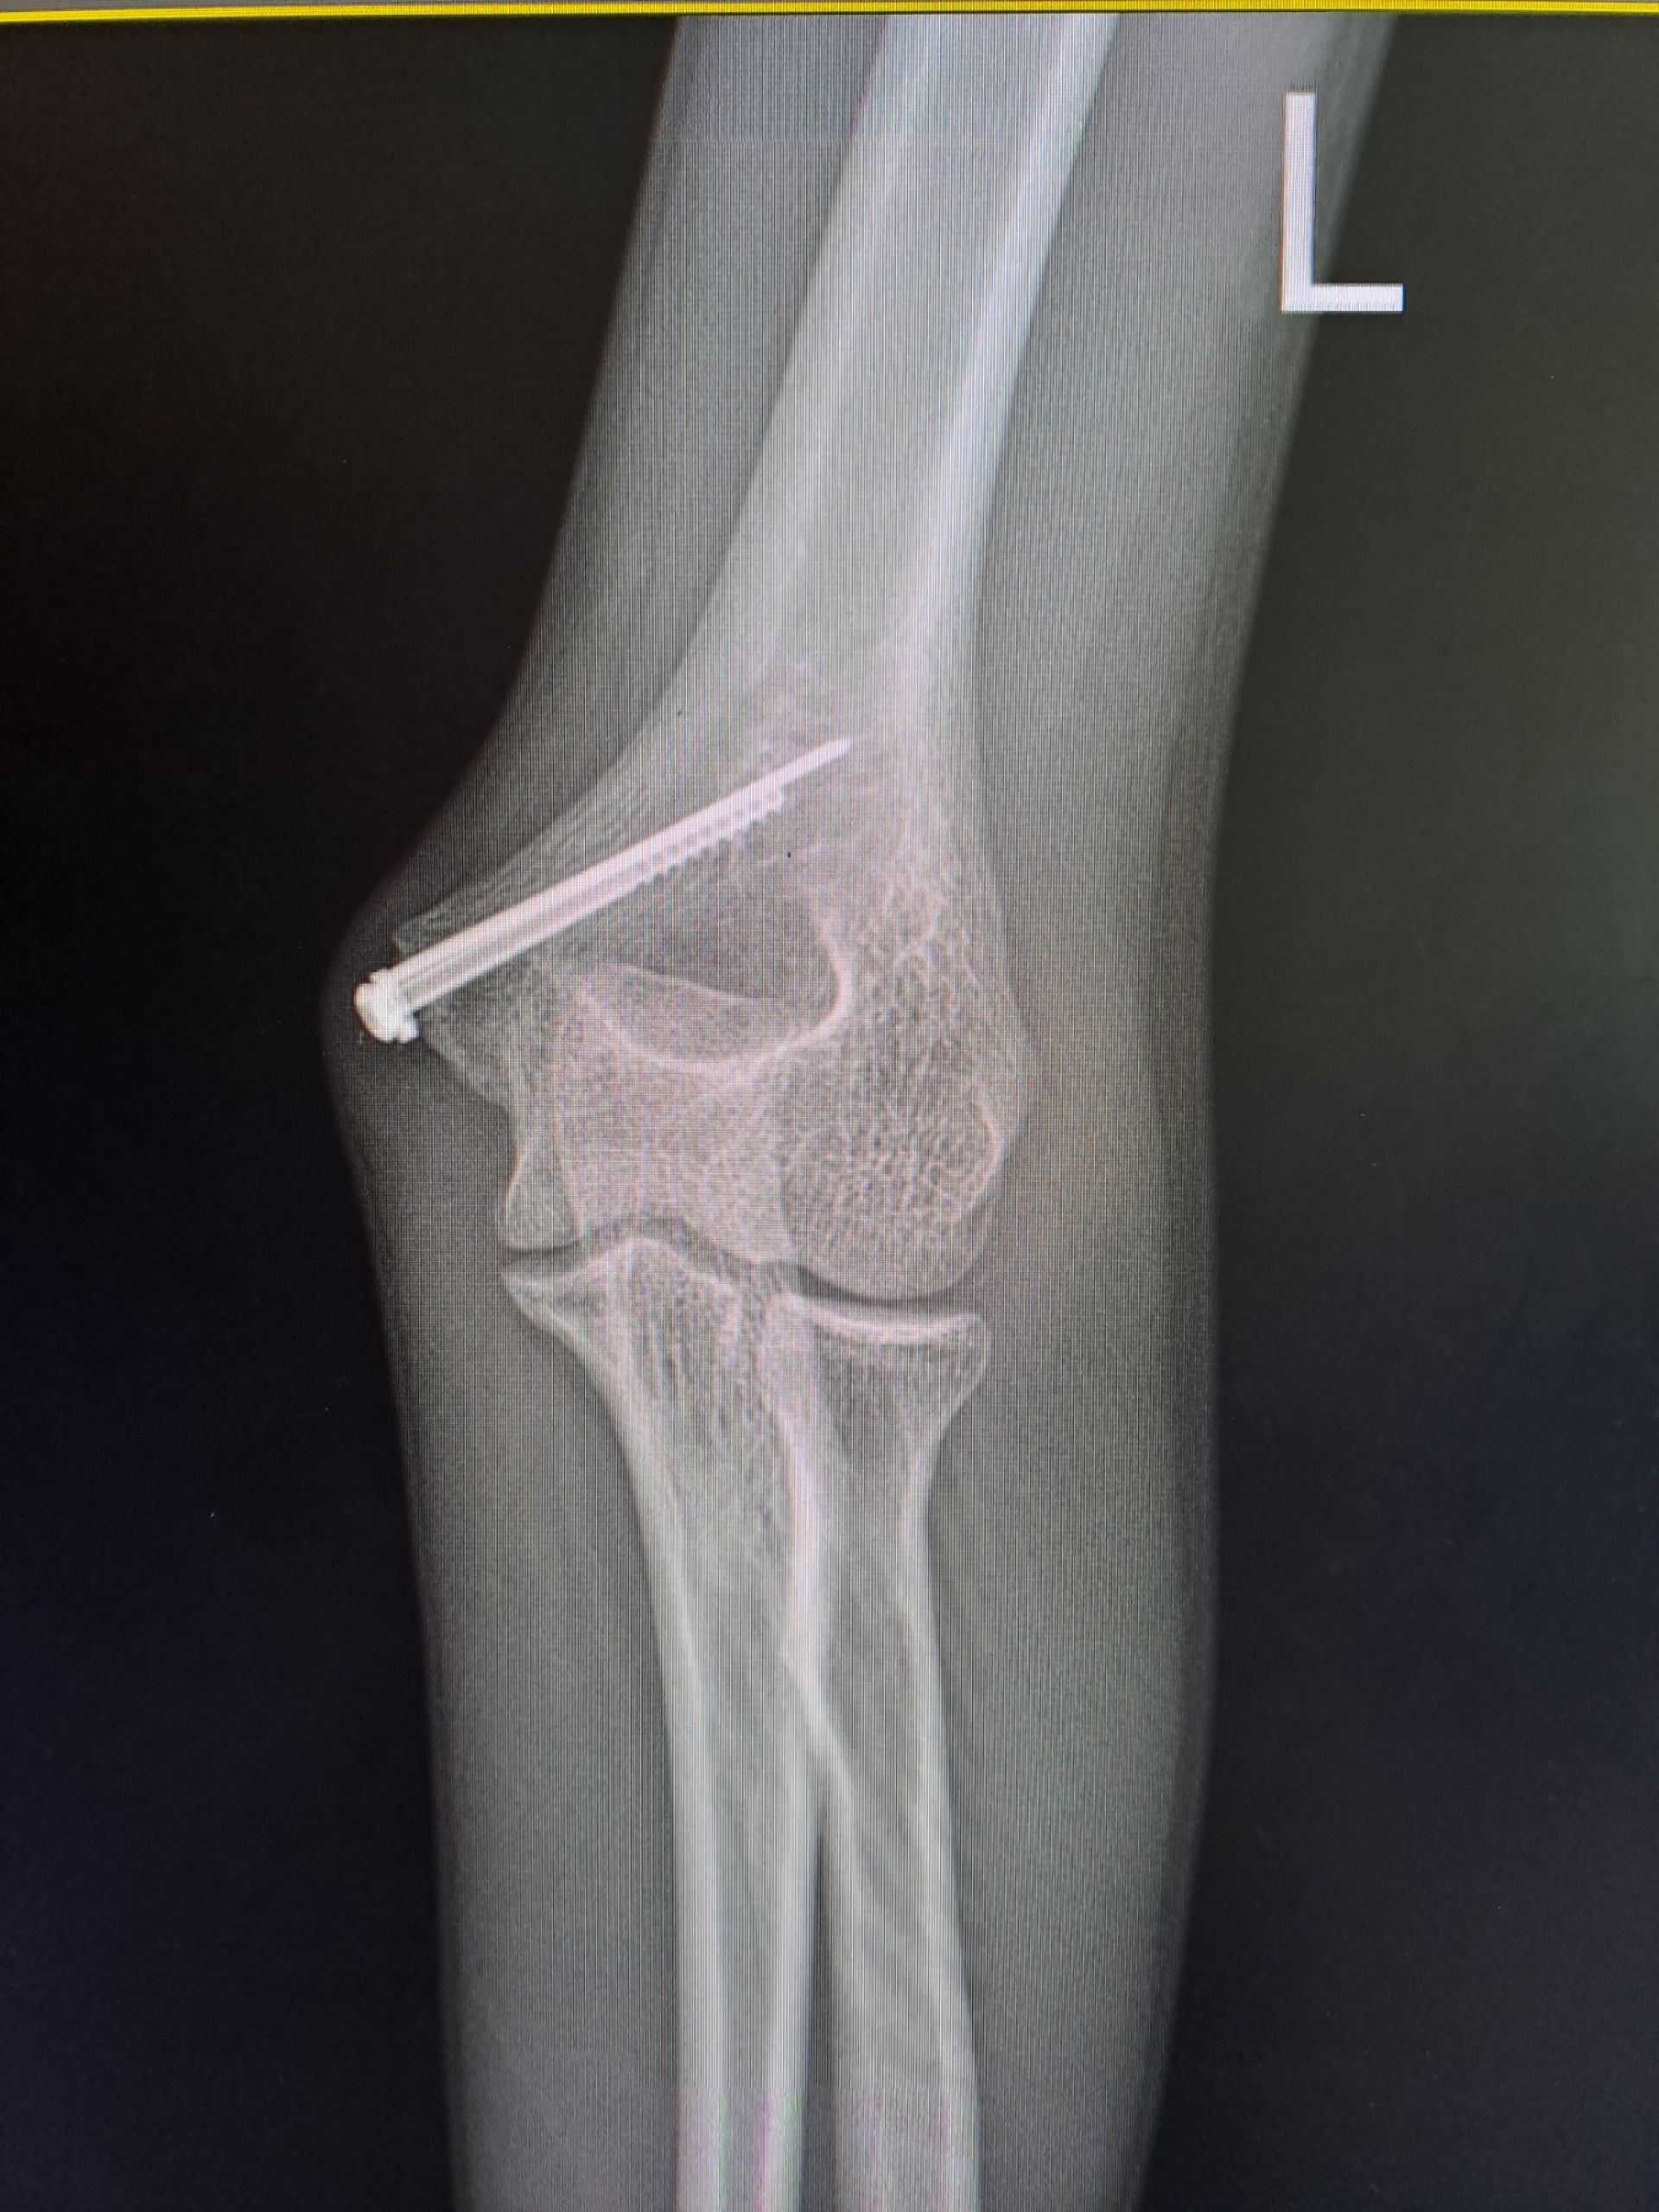

Хлопчик потрапив до травмпункту з вираженим болем та сильною деформацією ліктя. Рентген підтвердив найгірші побоювання медиків: закритий вивих передпліччя разом із переломом плечової кістки. Таке ушкодження вважається нестабільним — це означає, що суглоб буквально «розійшовся», а зв’язки та капсула зазнали значних розривів, передає Вінницька обласна дитяча клінічна лікарня.

- Точне співставлення: уламки кістки зіставили до міліметра, повернувши їм анатомічну форму.

- Стабільна фіксація: щоб кістка правильно зрослася, її закріпили спеціальним гвинтом та спицею. Це дозволило не тримати руку в гіпсі занадто довго і почати рухи раніше.